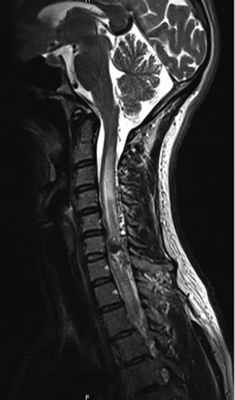

В стационаре выполнили МРТ шейного отдела позвоночника (рис. 1) и селективную спинальную ангиографию. По данным ангиографии, на уровне СVI—СVII позвонков выявлена спАВМ гломусного типа с наличием интранидальных аневризм и кровоснабжением из корешковых артерий, отходящих от левой позвоночной артерии и восходящей артерии шеи левого щитошейного ствола (рис. 2, а—в). Венозный дренаж осуществлялся в спинальные вены и венозное сплетение спинного мозга (рис. 3).

Рис. 1. Магнитно-резонансная томография шейного отдела позвоночника до операции.

Пояснения в тексте.

На МРТ шейного отдела позвоночника на вторые сутки после операции определялось уменьшение зоны отека спинного мозга выше и ниже АВМ. Через 3 мес выполнена контрольная селективная спинальная ангиография (рис. 6, а, б) и МРТ шейного отдела позвоночника (рис. 7), по данным которых признаков функционирования АВМ не выявлено. Клинически отмечено улучшение в виде полного регресса верхнего левостороннего монопареза и чувствительных расстройств.

Рис. 7. Магнитно-резонансная томограмма шейного отдела позвоночника через 3 мес после операции.

Признаков функционирующей спинальной артериовенозной мальформации не выявлено. Отек спинного мозга полностью регрессировал.